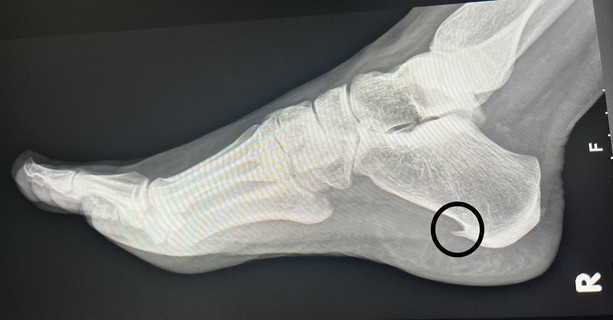

Petni trn: Uzrok, simptomi i metode liječenja

Petni trn, poznat i kao plantarni fasciitis, predstavlja jednu od najčešćih i najneugodnijih tegoba povezanih sa stopalima. Ova pojava nastaje usljed upale plantarne fascije, tkiva koje se proteže duž donjeg dijela stopala, od pete do prednjeg dijela stopala. Bol koja se javlja može biti izuzetno intenzivna i može značajno ometati svakodnevne aktivnosti, kao što su ustajanje, hodanje, pa čak i jednostavne radnje poput penjanja uz stepenice. Ovi simptomi često dovode do frustracije i kvaliteta života se može znatno smanjiti.